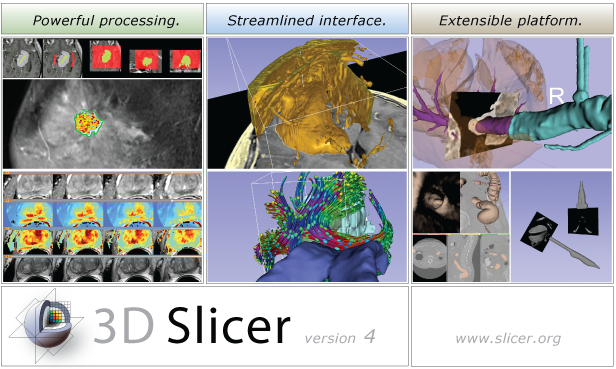

| Summary | What is 3D Slicer | Slicer 4.3 Highlights | Slicer Extensions | Other Improvements, Additions & Documentation |

The community of Slicer developers is proud to announce the release of Slicer 4.3.

- Slicer 4.3 introduces

- a new App store, called the extension manager, for adding capabilities to Slicer. Close to 40 plug-ins are currently available.

- close to 500 feature improvements and bug fixes lead to improved performance and stability.

- augmentation of many modules.

- improved workflows in registration and dMRI

- the multivolume explorer allows interaction with time series and DCE data.

- major improvements to the DICOM module

- a new Markups module to streamline the use of fiducial lists

- Click here to download Slicer 4.3 for different platforms and find pointers to the source code, mailing lists and bug tracker.

- Please note that Slicer continues to be a research package and is not intended for clinical use. Testing of functionality is an ongoing activity with high priority, however, some features of Slicer are not fully tested.

- The Slicer Training page provides a series of courses for learning how to use Slicer. The portfolio contains self-guided presentation and sample data sets.

What is 3D Slicer

Slicer is a community platform created for the purpose of subject specific image analysis and visualization.

- Multi-modality imaging including, MRI, CT, US, nuclear medicine, and microscopy

- Multi organ from head to toe

- Bidirectional interface for devices

- Expandable and interfaced to multiple toolkits